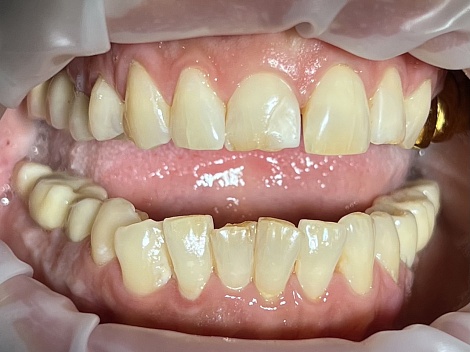

Комплексное пародонтологическое лечение с использованием диодного лазера и ортопедическое восстановление зубов

До

После

Услуги:

Лечение пародонтита

Заболевания:

Пародонтит,

Разрушение зубов

Стоматология

«Все свои!» м.Химки